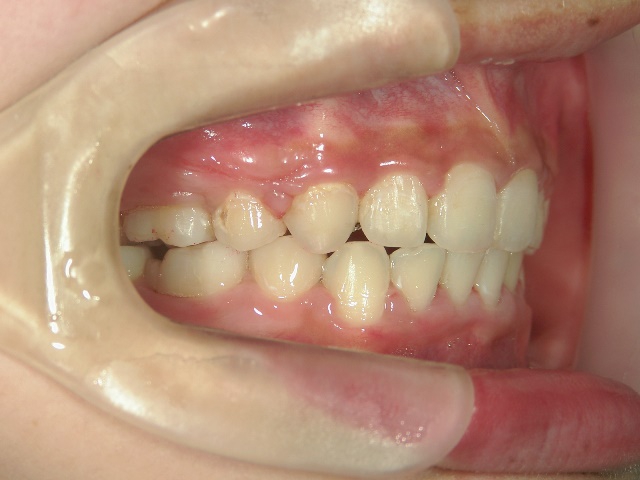

矯正歯科 治療前矯正歯科 治療前

矯正歯科 治療前 左右上下4番  計4本抜歯

no.18_2196_治療前_右.jpgno.18_2196_治療前_正面.jpgno.18_2196_治療前_左.jpg